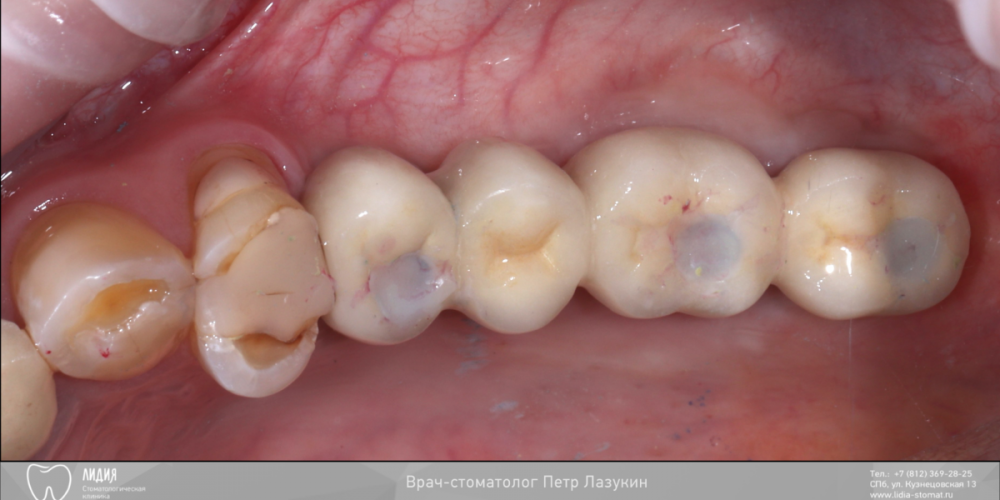

pit Опубликовано 22 декабря, 2021 Поделиться Опубликовано 22 декабря, 2021 Всем привет! Клинический случай. Реферативный пациент. В анамнезе несостоятельная костная пластика и несостоятельный синус-лифтинг (или даже два). Выбрана тактика: имплантация в позиции 25 27 28 (под углом 45 градусов) одномоментно с ОСЛ. В случае очередной неудачи протезирование было бы выполнено протезирование компромиссной конструкцией с опорой на 25 28 импланты. Во время операции произошел полный разрыв слизистой пазухи. Палатинальная стенка была скелетирована и к ней подшита мембрана с формированием купола. Уложен графт ИНТЕРОС, установлены импланты Хай-Тек. Швы. Протезирование МК коронками с винтовой фиксацией с уровня МЮ и платформ через 12 месяцев 13 1 2 Ссылка на комментарий